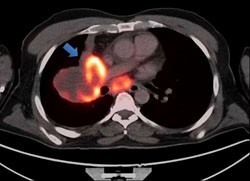

Παραδείγματα πότε μπορεί να βοηθήσει η εξέταση (ΕBUS) στη διάγνωση

Εικόνες από τη διαδίκασια της ταχείας βιοψίας μέσα στην αίθουσα ενδοσκόπησης